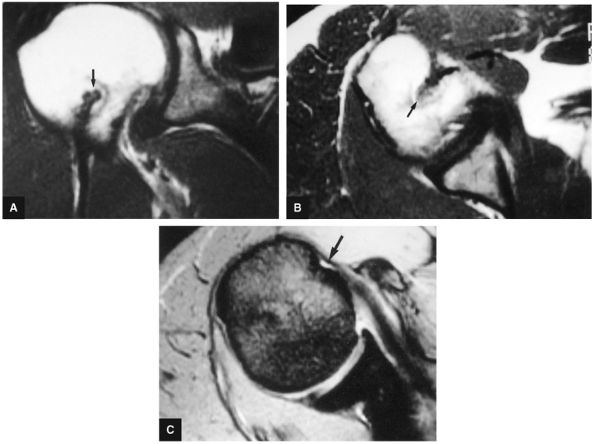

![]() |

FIGURE 8.7 ● (A) Normal central point (red cross) of glenohumeral rotation with arm positioned in abduction and external rotation. This position of function is achieved by placing the hand behind the head with the patient in the supine position. (B) Axial oblique ABER (abduction and external rotation) anatomy illustrated at the level of the IGHL labral complex posterior to the ABER section through the supraspinatus tendon. The MGHL and conjoined rotator cuff tendon are visualized superior to this section, whereas the inferior labrum and teres minor tendon are demonstrated inferior to this section in the ABER sequence.

FIGURE 8.8 ● Functional anatomy of the inferior glenohumeral ligament (IGL). (A) A coronal localizer obtained with the arm placed in 90° of abduction (i.e., the position of function of the IGL) and external rotation. (B) The corresponding axial image through the glenohumeral joint shows a taut IGL (small straight arrows) and intact anterior labrum (curved arrow).